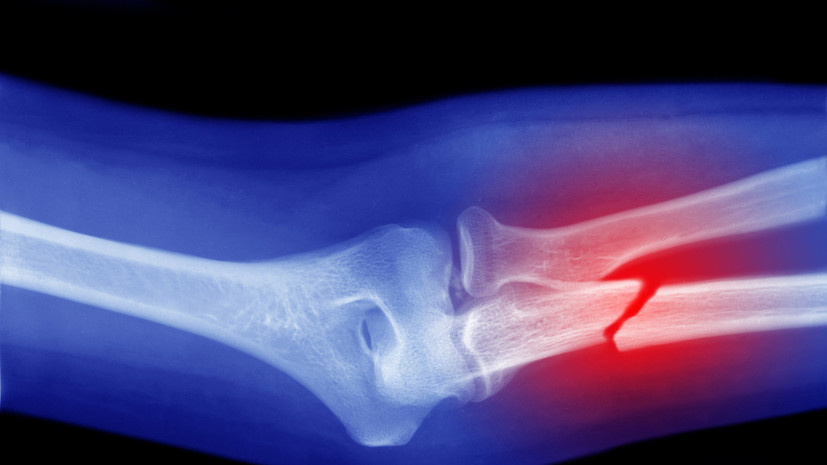

Врач Бештоев: в случае перелома отёк и гематома появляются очень быстро

Травматолог-ортопед Разиуан Бештоев рассказал, что при переломе немедленно возникают острая боль, отёк и гематома. В беседе с «Газетой.Ru» специалист отметил, что при переломе костей нижних конечностей синяки и кровоподтёки могут распространиться по всей ноге, а также на пальцы или стопу. «Уже через несколько минут может стать заметной деформация — видимое искривление кости или неестественное положение конечности», — сказал Бештоев. По словам специалиста, при ушибе отёк и синяк будут развиваться медленно. Кожа может начать менять цвет только к вечеру или даже на следующий день, добавил врач. Ранее врач-остеопат, руководитель авторской клиники остеопатии Дмитрий Симкин рассказал, что регулярная боль в грудине может быть признаком артроза рёберно-грудинных и грудинно-ключичных сочленений.